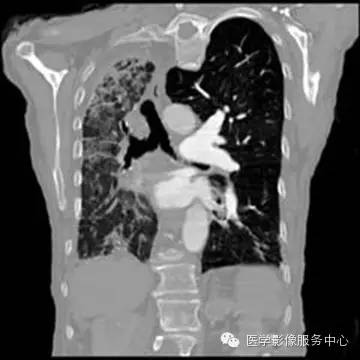

胸部CT平扫显像能力优于X线平片,显示UAPA典型征象更明显,偶尔可见患侧肺动脉段缺如。当见患侧失去正常肺小叶结构时,提示原发病导致肺泡发育障碍;另外可见肺纹理纤细走行僵直、肺门菲薄,可伴发肺大泡、间质改变及其他肺部病变。